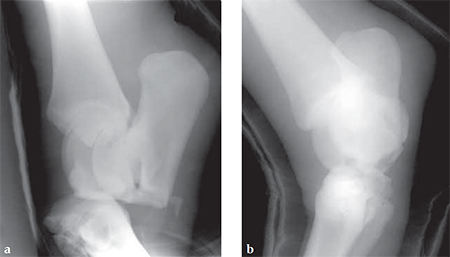

A 14-year-old Trakehner mare sustained a luxation of the proximal intertarsal joint (calcaneus and talus are displaced palmarly).

(Case provided by Alan Ruggles, Lexington Kentucky, USA)